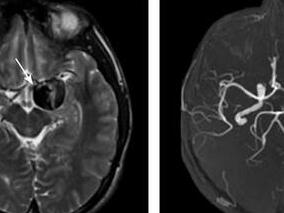

1小时条评论1 病例简介 例1 患者女,11岁,主因阵发性头痛9年,加重10天于2009年6月15日收入院。患者9年前无明显诱因出现头痛,为右额颞部钝痛,持续1~2小时后缓解,之后每年发作4~5次。10日前再次头痛发作,伴左侧肢体无力,到当地医院就诊,CT示右侧额颞占位,考虑动脉瘤...

1小时条评论1 病例简介 患者男,40岁。主因突发头痛、呕吐42小时于2009年11月2日入院。患者于入院前42小时在活动中突发剧烈头痛伴有恶心呕吐。到当地医院就诊,CT示蛛网膜下腔出血(图4.3-1)。为进一步诊治到我院就诊。急诊DSA示前交通动脉瘤(图4.3-2),立即给予血管内动脉...

1小时条评论1 病例简介 患者男,51岁,因右上肢麻木,右下肢活动力弱2个月于2009年7月17日就诊于我院门诊。患者2个月前无明显诱因出现右上肢麻木,伴右侧面部发热感,自觉右下肢活动力弱,但不影响行走。左侧肢体均无感觉及活动异常。 既往史:高血压病史10余年,血压最高200...